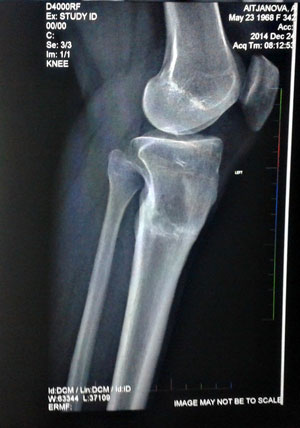

рентген от 24.07.2014г.

Здравствуйте, А.! По результатам рентгена: сращение хорошее, но: если Вас ничего не беспокоит, то Н.Н. советует ещё походить до 18 августа, учитывая возраст и степень деформации. После 18.08. ждём на снятие аппаратов (дату приезда сообщите, планируйте приезд в будние дни).

Чувствую себя хорошо. Перед снятием делала . рентген снимок, на снимке виден отломок, хотела бы чтобы Николай Николаевич посмотрел мой снимок и

может быть дал какие-нибудь дополнительные рекомендации, снимок у Анны Викторовны.Через неделю собираюсь на работу, работа у меня не сидячая,

можно ли мне ходить без костылей, просто с бандажом.